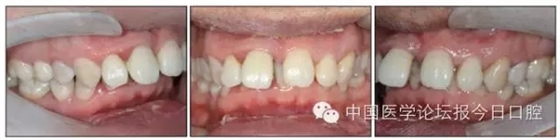

本病例為慢性牙周炎致前牙漂移、深覆(牙合)患者。本病例采用無托槽隱形矯治技術(shù)進行治療。無托槽隱形矯治器具有可摘戴、便于口腔衛(wèi)生維護和牙周治療的優(yōu)點,更適合于伴有牙周炎的錯(牙合)畸形患者的治療。 患者男,48歲,前牙有縫、前突求診。 患者面部對稱,側(cè)面觀上頜前突,下頜后縮。 口內(nèi)情況:恒牙列,24、34、44缺失,磨牙Ⅲ類關(guān)系,上牙列散隙,上前牙扇形漂移。前牙深覆(牙合)、深覆蓋??谇恍l(wèi)生較差,11與12間牙齦乳頭紅腫,多個牙探診有牙周袋形成,11松動Ⅰ度,余切牙松動(-),患者面像及口內(nèi)像如圖1、2所示。 圖1 治療前面像 圖2 治療前口內(nèi)像 全口曲面體層片(圖3)顯示,患者全牙列牙槽骨吸收;根尖片(圖4)示11近中牙槽骨角形吸收已達根尖1/3,21牙槽骨嵴頂吸收至根1/2,23牙槽骨近中骨板角形吸收至根1/2。磨牙區(qū)骨嵴頂吸收3mm。治療前頭顱側(cè)位片見圖3,治療前ODS模型見圖5。 圖4 治療前根尖片 圖5 治療前ODS模型 牙型:安氏Ⅲ類。骨型:Ⅱ類。面型:上頜前突,下頜后縮。 問題列表為:①上牙列間隙;②上切牙病理性牙移位;③前牙深覆(牙合)、深覆蓋;④24、34、44缺失;⑤慢性牙周炎。 矯治目標包括:①排齊牙列,關(guān)閉牙列間隙;②改善前牙深覆(牙合)、深覆蓋;③改善牙周狀況。 矯治設(shè)計有:①牙周基礎(chǔ)治療與維護。②壓低、內(nèi)收上切牙,關(guān)閉上牙列間隙。③壓低下切牙,伸長下后牙,整平Spee曲線,改善前牙覆(牙合)、覆蓋。 患者進行全口齦上潔治、齦下刮治,口腔衛(wèi)生宣教,并按牙周醫(yī)師的要求,每2~3個月行牙周檢查與治療。 牙周基礎(chǔ)治療結(jié)束3個月,開始隱形矯治。于14、25、35、36、45、46上粘接附件(圖6),于16、26(牙合)面粘接(牙合)墊。 圖6 ODS設(shè)計附件粘接圖示 矯治過程中注意(牙合)墊是否脫落或磨損,及時修補。 注意上前牙內(nèi)收時有無咬合干擾,及時調(diào)(牙合)。下頜前磨牙伸長到位后,磨除16、26(牙合)墊。 下頜佩戴第24步矯治器時,分別在36、37、46、47的頰、舌側(cè)粘接舌扣,矯治器上預(yù)留伸長空間,用3/16英寸、3.5盎司皮圈牽引,輔助伸長下磨牙(圖7)。 患者共戴用矯治器上頜32步,下頜26步。 矯治后,牙列間隙關(guān)閉,面型及覆(牙合)覆蓋改善。11根尖片(圖8)顯示,治療后較治療前,牙周支持組織增加,牙槽骨角形吸收區(qū)水平向縮小0.3mm,垂直向縮小0.6mm。11松動Ⅰ度,余切牙無松動。 圖8 治療后根尖片 圖9 治療后口內(nèi)像 圖10 治療后X線檢查 圖11 治療后ODS模型 正畸-牙周聯(lián)合治療對于牙周組織的影響 多學(xué)科綜合治療牙周炎患者不再是正畸治療的禁忌證。良好的牙周治療為正畸治療中的牙齒移動打下堅實基礎(chǔ),而正畸治療排齊牙齒、去除(牙合)干擾,有利于牙周健康。 牙周炎患者的正畸治療必須在牙周炎癥得到控制后才能進行,否則,菌斑會隨著牙齒的移動,特別是壓低而使牙周炎癥加重。牙周炎的正確診斷、牙周炎癥控制、正畸治療中和治療后的認真維護是治療成功的關(guān)鍵。根據(jù)臨床需要,一般每2~4周做一次潔治,每3個月進行牙周評估,同時患者必須進行非常良好的日??谇恍l(wèi)生維護。 固定矯治器使得牙周檢查、潔治和日??谇恍l(wèi)生維護變得困難,隱形矯治器可自行摘戴,便于患者日常維護和牙周治療,節(jié)約時間,提高菌斑控制效果。 有臨床研究表明,對于存在(牙合)創(chuàng)傷,伴有角形吸收的患牙,經(jīng)過牙周翻瓣手術(shù)控制住牙周炎癥后,使用正畸輕力壓低患牙,可以改善牙槽骨吸收的程度,并獲得一定程度的牙周新附著。本病例切牙壓低后,原來的牙槽骨吸收有改善。 病理性牙移位 病理性牙移位(PTM)在重度牙周炎患者中的發(fā)生率為30%~50%,且常見于上前牙區(qū)。其主要由于牙周支持組織喪失尤其是骨組織的丟失,咬合因素(如后牙缺失、前牙深覆牙合、牙合創(chuàng)傷等),頰舌唇肌力量不平衡及牙周和根尖周組織炎癥所致,是牙周炎患者要求正畸治療的主要原因之一。 PTM須通過正畸、牙周聯(lián)合,有時須配合修復(fù)才能達到理想的治療效果。正畸治療通常是壓低牙齒,臨床研究表明,牙周手術(shù)配合正畸壓低可以產(chǎn)生新附著,有利于PTM牙周組織的恢復(fù)。 本病例右上中切牙牙槽骨角形吸收,在盡量保證治療前后根尖片投照角度一致的情況下,以鄰牙作為校準,在根尖片上對治療前后的骨量進行評價,治療后牙槽骨角形吸收區(qū)水平向縮小0.3 mm,垂直向縮小0.6mm。盡管根尖片并不能說明骨量改變,但從影像學(xué)上能看到骨吸收區(qū)域有所減小。 無托槽隱形矯治器矯治牙周病的優(yōu)勢 無托槽隱形矯治器具有可摘戴、便于口腔衛(wèi)生維護和牙周治療的優(yōu)點,更適合于伴有牙周炎的錯(牙合)患者的治療;同時,無托槽隱形矯治器佩戴后具有牙弓夾板和(牙合)板的作用,可有效減少側(cè)向力,有利于牙周的恢復(fù)和減輕牙齒松動;由于無托槽隱形矯治器的設(shè)計是在三維數(shù)字模型上進行的,每個矯治器移動牙齒的數(shù)量和每個牙齒的移動距離可以得到量化控制,因而可以根據(jù)患者牙槽骨水平和對矯治力的耐受情況個性化設(shè)計矯治力,并且可以根據(jù)矯治中牙齒移動情況調(diào)整后續(xù)矯治器的設(shè)計。 有關(guān)磨牙伸長 單純使用無托槽隱形矯治器同步伸長后牙比較困難。該病例先使用磨牙(牙合)墊打開咬合,通過矯治器伸長前磨牙,在前磨牙建立咬合后,磨除磨牙上的(牙合)墊,通過輔助牽引伸長磨牙,最終達到伸長后牙、整平Spee曲線的目的。 史真,主任醫(yī)師,現(xiàn)任北京黃寺整形外科醫(yī)院口腔科主任,第四軍醫(yī)大學(xué)口腔正畸學(xué)碩士,為世界正畸醫(yī)師聯(lián)盟(WFO)會員、全軍口腔醫(yī)學(xué)專業(yè)委員會委員、中華口腔正畸專業(yè)委員會委員、中華醫(yī)學(xué)美學(xué)與美容學(xué)會齒科美容學(xué)組成員、北京口腔醫(yī)學(xué)會兒童口腔專業(yè)委員會常務(wù)委員、北京口腔醫(yī)學(xué)會正畸專業(yè)委員會委員、《中華醫(yī)學(xué)美學(xué)與美容》雜志審稿專家,是我國最早開展無托槽隱形矯治技術(shù)的口腔醫(yī)師之一。